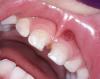

Здравствуйте девочки! Подскажите пожалуйста у дочи на верхней десне какая та шишка! Что это может быть может кто то сталкивался? Фото в комментариях